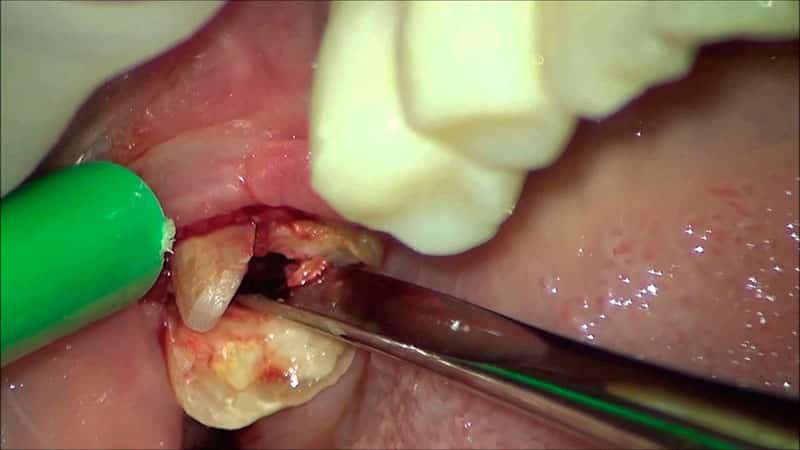

Зубы мудрости в настоящее время рассматриваются как рудиментарные органы, подобно аппендиксу. Они не причиняют вреда, но и особой пользы не приносят. Однако изменение рациона и образа жизни привело к уменьшению челюстной кости, и для многих людей эти «остатки предков» становятся причиной различных проблем. В таких случаях удаление зуба мудрости (фото можно увидеть в нашей галерее) становится необходимым. Именно с этим связаны многие страхи и слухи, касающиеся негативного влияния «восьмерок» на здоровье и качество жизни.

- Сложная процедура требует обязательного участия стоматологического хирурга. Такое вмешательство чаще всего необходимо при нарушениях прорезывания, гнойных инфекциях и перикоронарите. Удаление «восьмерки», которое проводится под действием сильных обезболивающих, часто требует хирургического вмешательства не только на мягких тканях, но и на кости, так как корни могут быть прочно вросшими в челюсть. После операции на лунку накладываются прочные швы из нерассасывающихся материалов. Врачебный контроль осуществляется каждые один-два дня. Швы снимаются после полного заживления раны.